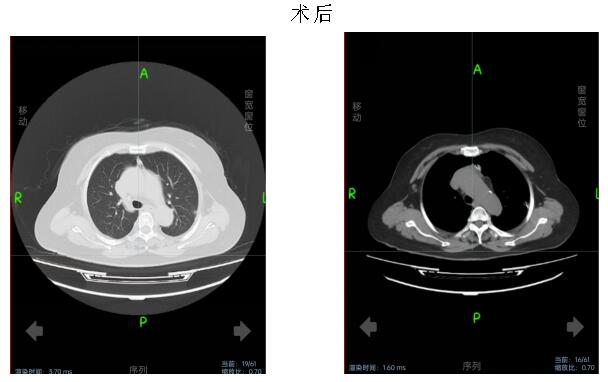

术中,在麻醉手术科配合下,李卫国带领胸外科团队为患者行胸腔镜经剑突肋缘三孔式胸腺病损切除术。术中送冰冻,30分钟后病理报告提示胸腺瘤,术后生命体征平稳,给予镇静止痛、营养支持等对症治疗。术后第3天复查胸部CT未见明显积液积气。患者无特殊不适。